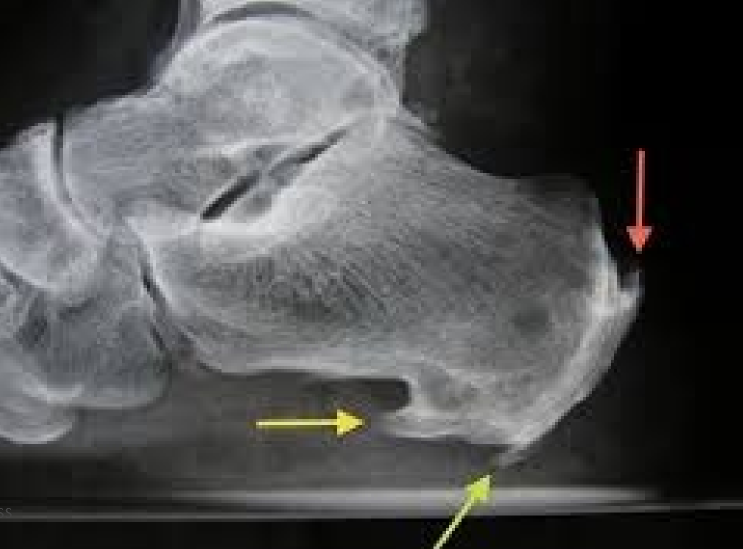

Os Trigonum -what is it? -cause–uni or bi -how common? -what populations have an increase in prevalence

-During ossification the secondary ossification center of the talus (usually the tubercle of the talus) fails to unite with body of the talus OR the ossification center may have fraction and never unite to body of talus -applied stress when younger (forceful plantarflexion); usually occurs bilateral -25% of population -ballet dancers and soccer players

Calcaneal osteophytes -how location impacts patient

-posterior: develops on back of heel at insertion of achilles tendon -inferior: calcification lies superior to plantar fascia at insertion of plantar fascia